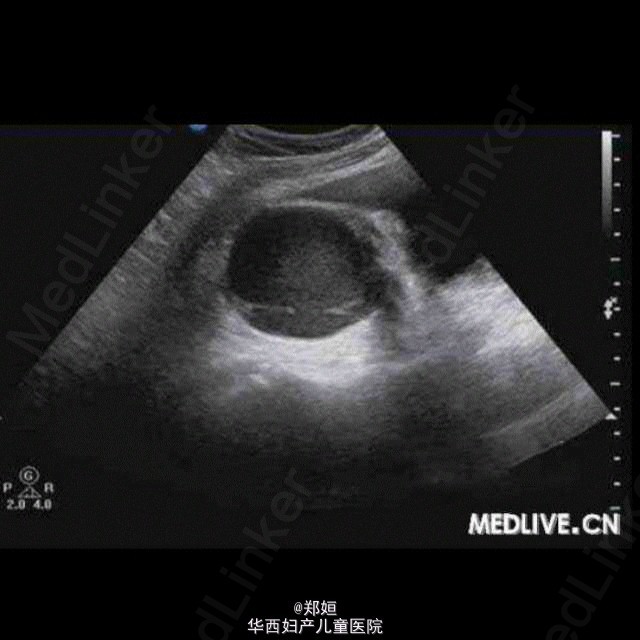

病历资料:女,34岁,6年前体检发现左附件区有一直径为2 cm的肿物,因肿物体积较小而未治疗。5年前患者无明显诱因地出现月经期腹痛 ,伴腰酸腹胀逐渐加重,须服止痛药缓解,B超复查显示,盆腔肿物体积增大。超声检查:子宫肌层回声欠均匀,子宫后壁肌间隐约可见3.8 cm×3.5 cm×3.7 cm中等回声包块,边界欠清,点状血流信号(图1)。右附件可见6.7 cm×5.8 cm×5.3 cm囊性包块,边界清,外形规则, 内为液性暗区伴细密光点,囊壁可见点状血流信号(图2和图3);子宫左上方可见6.1 cm×4.5 cm×4.6 cm囊性包块,边界清,外形尚规则 ,内为液性暗区伴细密光点,内可见分隔,隔壁可见条状血流信号(图4)。 诊断:子宫增大;子宫腺肌症;双附件区囊性包块。 术中所见:子宫前位,宫体球形,质硬;子宫后壁外突瘤核,界限不清。双侧卵巢均囊性增大,囊肿内为巧克力样物质,均为多房,与阔韧 带后叶、乙状结肠和子宫后壁粘连。 http://case.medlive.cn/obgyn/case-article/show-46213_207.html